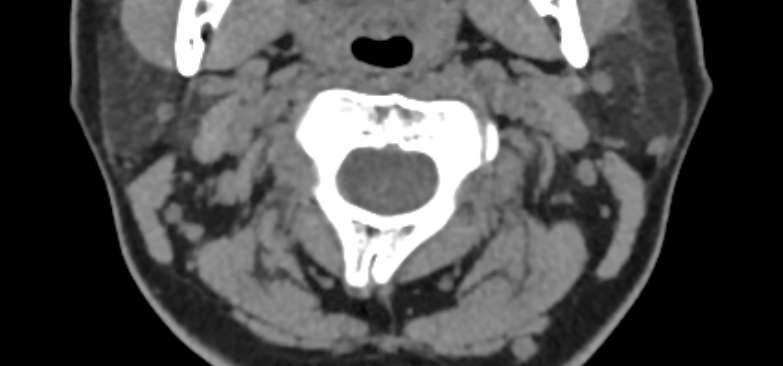

Одним из наиболее информативных методов диагностики заболеваний краниовертебрального перехода является мультиспиральная компьютерная томография с возможностью объемной реконструкции изображений. В основе методики лежит использование рентгеновского излучения. КТ позволяет детально визуализировать костные структуры позвонков, выявить нестабильность суставов, смещение зубовидного отростка и оценить степень сдавления спинного мозга.

При проведении мультиспиральной КТ можно диагностировать различные заболевания, в том числе, аномалии развития краниовертебральной области (как врожденного, так и приобретенного происхождения):

- смещение шейных позвонков в результате травм;

- дегенеративно-дистрофические заболевания данной области;

- воспалительные и аутоиммунные заболевания с поражением краниовертебрального перехода;

- опухолевые образования.